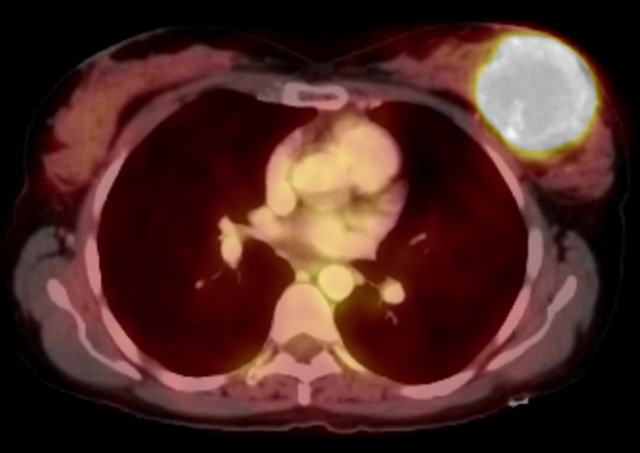

PET/CT

While PET/CT is more likely used to evaluate extent of disease in a patient with a known diagnosis, breast sarcomas may demonstrate avid FDG uptake6. (Figure 3).